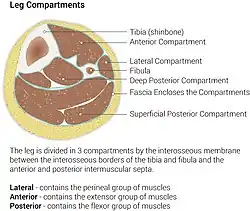

Diagram of leg compartments | |

The lateral compartment of the leg is a fascial compartment of the lower leg. It contains muscles which make eversion and plantarflexion of the foot.